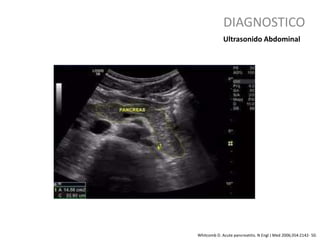

DIAGNOSTICO

Whitcomb D. Acute pancreatitis. N Engl J Med 2006;354:2142- 50.

Ultrasonido Abdominal